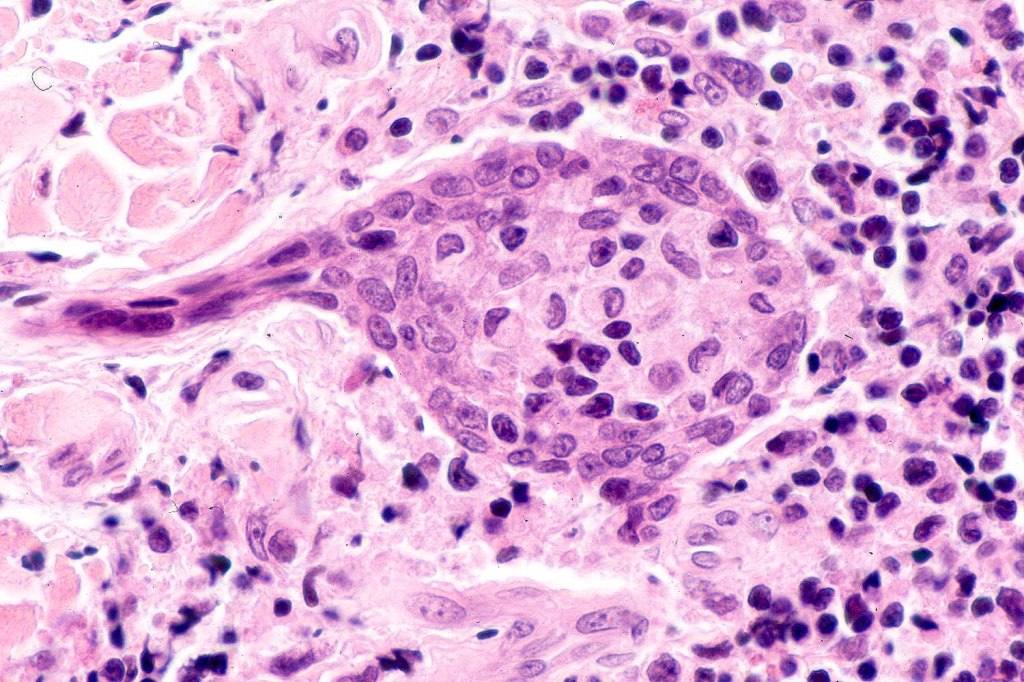

Histology may show epidermal involvement and folliculotropism. The characteristic feature is the presence of a heavy deep dermal atypical lymphocytic infiltrate surrouding and infiltrating the sweat gland & ductal epithelium. Variable numbers of Sézary cells may be present.